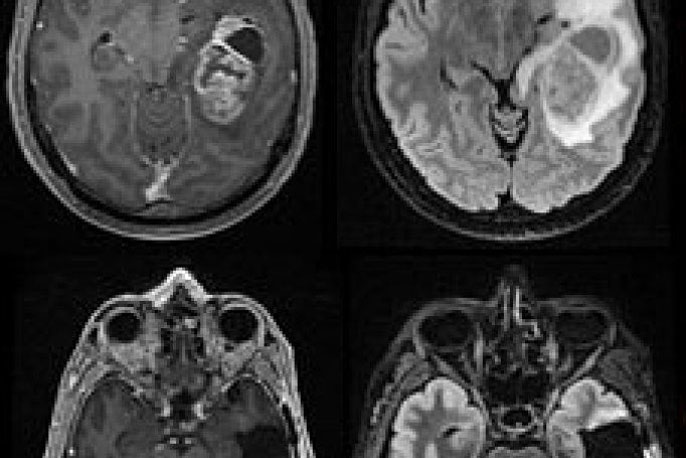

In one paper, research teams led by Wendell Lim, Ph.D., chair and Byers Distinguished Professor of cellular and molecular pharmacology, and Hideho Okada, M.D., Ph.D., the Kathleen M. Plant Distinguished Professor of neurological surgery, tested the system in glioblastoma, the most aggressive form of brain cancer that affects adults and children, and which physicians have yet to successfully treat with immunotherapies due to the complexity of the tumors. The team showed the new system, which uses a two-step process to hunt down cancer cells, could completely clear human patient-derived tumors from the brains of mice without the dangerous side effects or high risk of recurrence currently associated with immunotherapy treatment in solid tumors.

Experiments described in the paper show that this strategy is effective. In mice with human patient-derived glioblastomas, synNotch CAR-Ts wiped out tumors that weren’t cleared by normal T-cells or traditional CAR-Ts, with no signs of dangerous side effects.